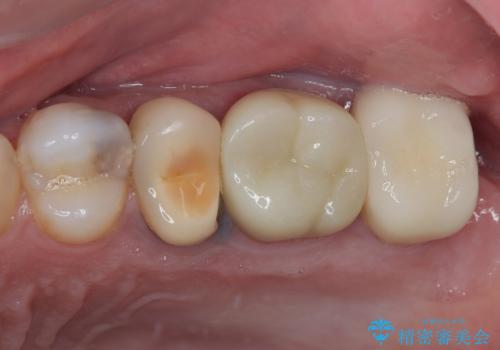

- 銀歯やむし歯でものが挟まるところが気になるとのことで来院された患者様です。

左上の奥歯は神経が失活しており、根管治療が必要な状態でした。

その他は銀歯のインレー(部分的な詰め物)が装着されており、それらはむし歯を除去した後にセラミックインレーにて修復治療を行い、左下と根管治療を行う左上の奥歯はオールセラミッククラウンにて補綴治療を行うこととしました。

目立っていた銀歯がなくなり、患者様には大変満足していただけました。